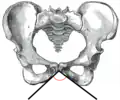

![]() Female pelvis (pubic arch labeled at bottom center) | |

Female subpubic angle